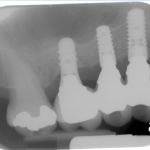

The bone used in a sinus lift may come from your own body (autogenous bone), from a cadaver (allogeneic bone) or from cow bone (xenograft). You will need X-rays taken before your sinus lift so the dentist can study the anatomy of your jaw and sinus. You also may need a special type of computed tomography (CBCT) scan. This scan will allow the dentist to accurately measure the height and width of your existing bone and to evaluate the health of your sinus.

After several months of healing, the bone becomes part of the patient’s jaw and dental implants can be inserted and stabilized in this new sinus bone.

If enough bone between the upper jaw ridge and the bottom of the sinus is available to stabilize the implant well, sinus augmentations and implant placement can sometimes be performed as a single procedure. If not enough bone is available, the sinus augmentation will have to be performed first, then the graft will have to mature for several months, depending upon the type of graft material used. Once the graft has matured, the implants can be placed.